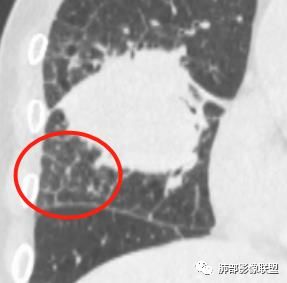

特别是远端物阻塞性改变,也支持外围来源

还有癌淋,低分化腺癌可以这样吧

1.本病例结合病理结果及影像综合分析,应该符合肉瘤样癌,上皮成分是腺癌为主;肿块的边缘毛刺、分叶及周围癌型淋巴管炎征象有符合腺癌的影像表现之处。

2.肿块巨大局部边缘膨隆、光整,坏死较彻底;明显跨叶生长(途经发育不全叶间裂或肺门,注意患者没有胸水),支气管阻塞伴推移等,这些更符合肉瘤的特性。